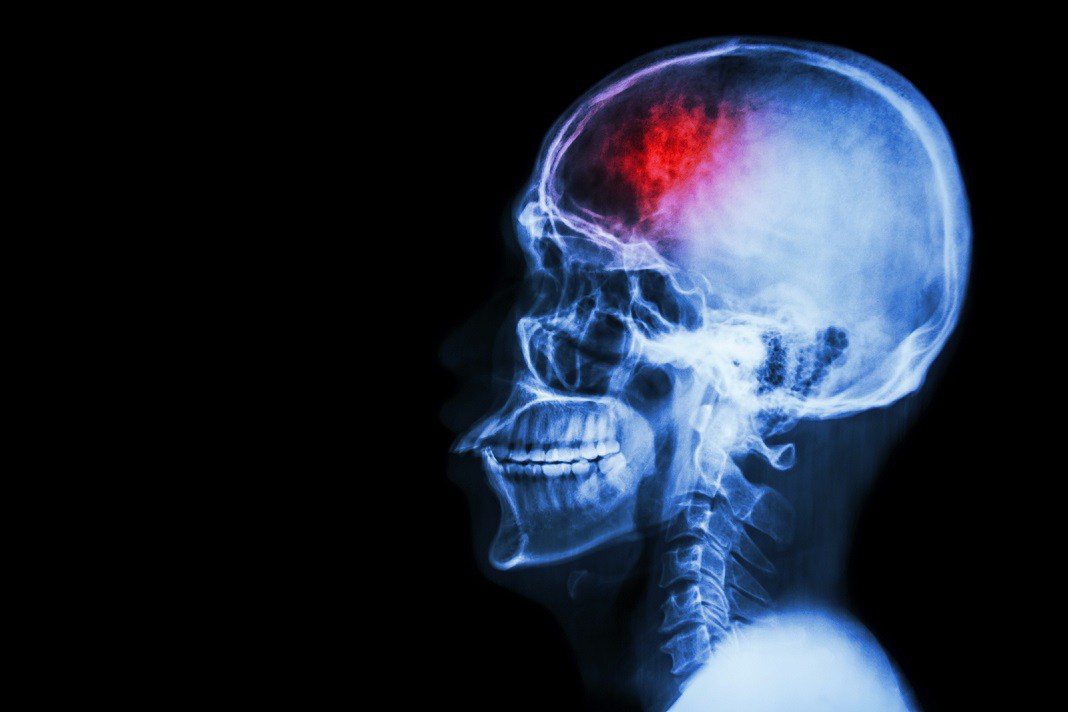

Learn about the causes of a stroke in the video from CHI Health below:

“Treating clots is a serious problem for all hospitals, and we take them very seriously as surgeons,” said cardiovascular surgeon and coauthor Alan Lumsden, M.D. in the press release. And he goes on to note the problems that still need to be overcome: “Although tPA and similar drugs can be very effective in rescuing our patients, the drug is broken down quickly in the blood, meaning we have to use more of it to achieve an effective clinical dose. Yet using more of the drug creates its own problems, increasing the risk of hemorrhage. If hemorrhage happens in the brain, it could be fatal.”